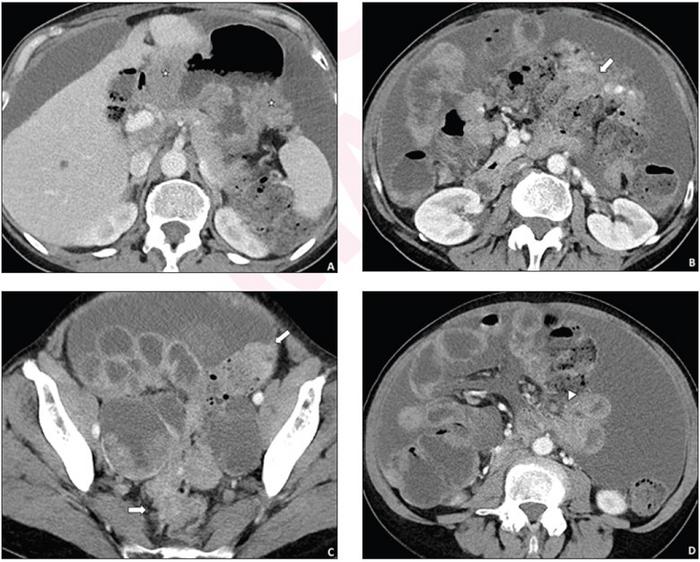

62-year-old woman who underwent pretreatment CT for suspected advanced ovarian cancer

image: Simple structured CT report described presence of peritoneal implants in 6 anatomic locations. Disease was considered resectable based on CT report, and primary debulking surgery was performed. However, this surgery yielded suboptimal resection. Axial contrast-enhanced images from pre-treatment CT show disease involvement of sites of residual disease at surgery that were not mentioned in the report, including the gastric wall (stars, A), colonic wall (arrows, B and C), and small bowel mesentery (arrowhead, D). view more

Ultimately, in patients who underwent CT before ovarian cancer treatment, involvement of surgically established unresectable or challenging-to-resect disease sites was mentioned in 37% (11/30) of simple structured reports, compared to 100% (13/13) of disease-specific synoptic reports. Moreover, all gynecologic oncology surgeons surveyed by the authors of this AJR accepted manuscript reported that synoptic reports impacted treatment selection and benefited their practice.